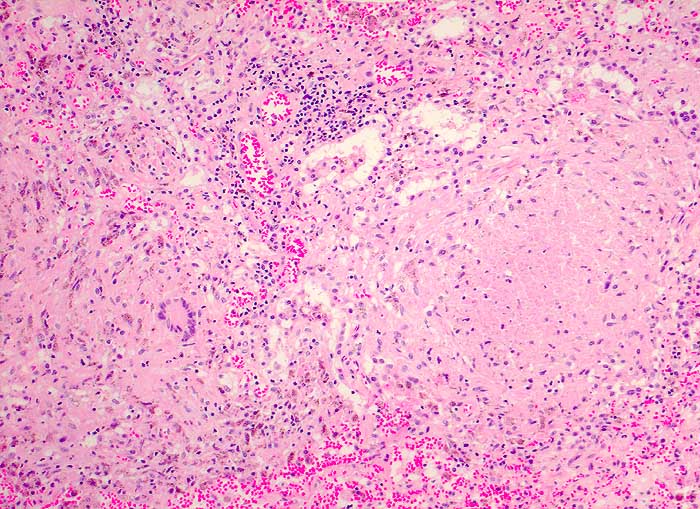

Tuberkulöse Lymphadenitis

Entzündung infektiös

Die meist atrophischen Epitheloidzellen sind oft nur schwer von Venulenendothelien unterscheidbar und sind nur relativ selten zu deutlich erkennbaren Granulomen zusammengeballt. Bei Vorliegen von verkäsenden Granulomen erscheint der Ausstrich feinkörnig-detritisch. Eine granulozytäre Entzündung muss bei AIDS Patienten an eine Tuberkulose denken lassen.